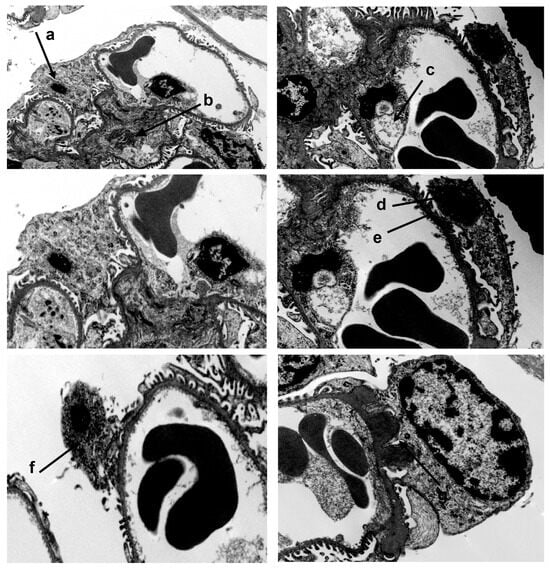

3.3. A20Δpodocyte Mice Exhibit Increased Glomerular Injury